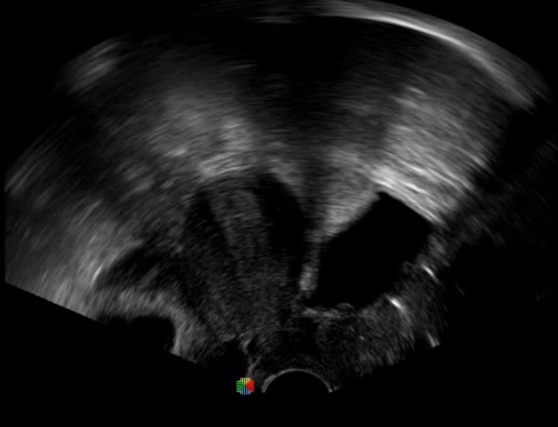

多數(shù)的生殖科醫(yī)生對(duì)于受精卵的植入采用憑經(jīng)驗(yàn)操作或是使用傳統(tǒng)腔內(nèi)探頭引導(dǎo),同樣存在手術(shù)空間小、受精卵放置位置不確定等風(fēng)險(xiǎn)。專業(yè)的宮腔專用探頭,配合專用的窺器使用,為醫(yī)生提供最大的手術(shù)視野。

胎移植臨床圖